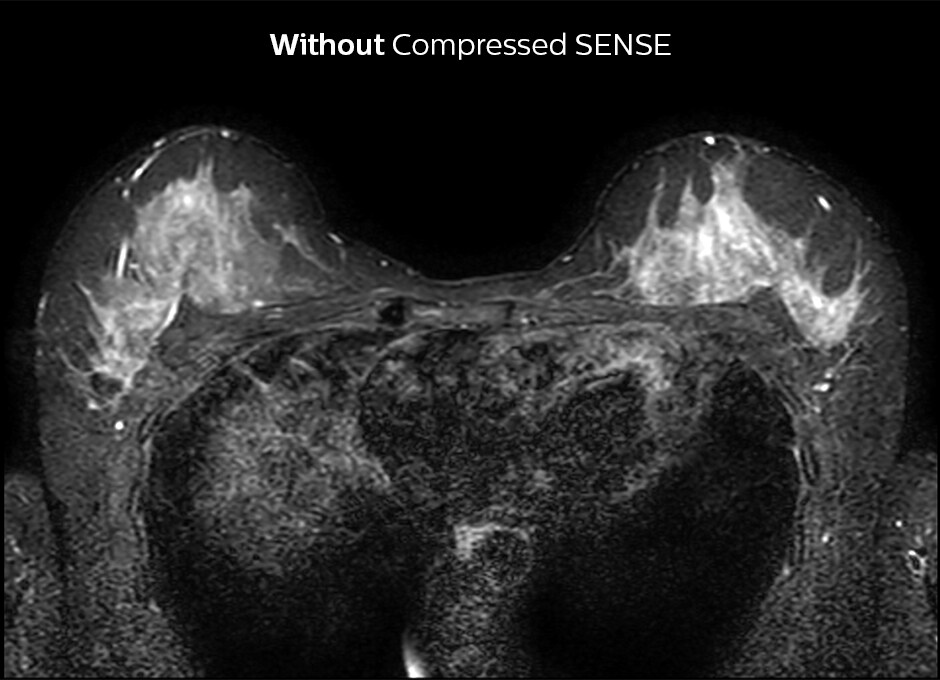

Up to 50% faster MRI scans with virtually equal image quality1

Philips Compressed SENSE is a cutting-edge MRI technology that significantly speeds up scans while delivering virtually equal image quality. By intelligently compressing data, it accelerates your existing MR scans by up to 50%, frees up time to improve your patient experience and can provide up to 60% higher resolution to enhance diagnostic confidence.1 Philips Compressed SENSE is suitable for all anatomies and can be used for all anatomical contrasts, in both 2D and 3D.

Compressed SENSE enables acceleration by up to 50% with the same resolution and virtually equivalent image quality as dS SENSE scanning. The time saved can boost productivity by enabling more patients per day.

1. Compared to Philips scans without Compressed SENSE.